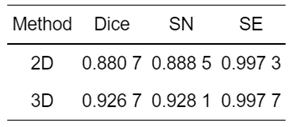

二维与三维检测网络结果对比:

为验证三维卷积神经网络,将二维检测网络与三维检测网络的实验结果进行了对比,图 16为二维检测网络收敛示意图.

对比图 16和12可知,三维检测网络的损失函数收敛拟合程度更佳,二维检测网络的训练和测试损失值为-0.875 9及-0.870 7,而三维检测网络可达到-0.909 4和-0.901 7,分别提升了3.35%和3.1%.

脑肿瘤二维检测网络与三维检测网络评价指标对比如表 3所示,与二维检测网络相比,三维检测网络Dice、SN和SE的结果分别提高了4.6%、3.96%和0.04%,证明了三维检测网络的可靠性.

表 3 二维与三维网络评价指标对比